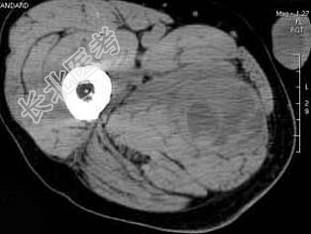

- 单项选择题男,30岁, 主诉右大腿肿块年余,逐渐增大, 局部胀痛及压痛,根据图像表现, 最可能的诊断是 ( )

D、横纹肌肉瘤